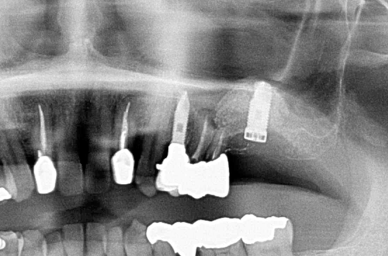

術前のCT画像、このように骨の厚みがほとんどありません

サイナスリフトとインプラント同時埋入しています。この場合だいたい9か月ほど

インプラントが骨に結合するまで待ちます

CTで人工骨がインプラントの周りに入っているのを確認しています。

サイナスリフトをする場合、CTがないと成功しているかの確認が難しいと思われます。